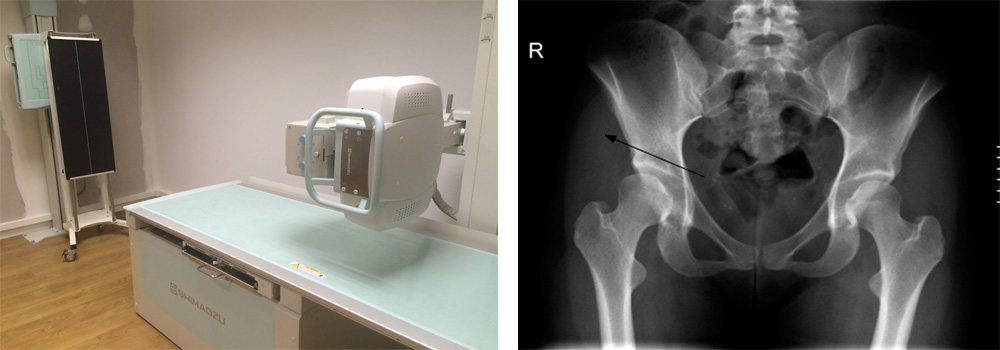

RADIOLOGIA CONVENCIONAL. RAYOS X RAYOS X DIGITAL CON TELEMETRÍA ÓSEA

"Alta resolución de imagen y capacidad de estudio de cuerpo completo". Proporciona la capacidad de realizar estudios específicos sobre cualquier parte del esqueleto en busca de posibles patologías. Leer más...

La telemetría ósea se trata de una radiografía realizada en bipedestación, es decir a de pie y a cierta distancia, permitiéndonos realizar un estudio de mayor o menor rango variando la distancia de disparo. Es esta forma se puede diagnosticar simultáneamente una zona amplia del sistema esquelético para la detección de anomalías u observar, por ejemplo, el estado de conservación de una prótesis en la cadera o en las extremidades inferiores. Posteriormente acudiendo a un software específico podemos evaluar el grado y nivel de alteración si existe, realizando una comparativa respecto a su nivel normal por ejemplo respecto a la curvatura ósea de una columna o de una pierna El Escoliograma y la Telemetría de miembros inferiores son radiografías que nos muestran toda la columna y las extremidades inferiores (cadera, piernas y pies). Con el Escoliograma podemos valorar desviaciones o curvaturas anómalas de la cadera, y con la Telemetría de los miembros inferiores se valoran dismetrías y otras alteraciones de las extremidades.